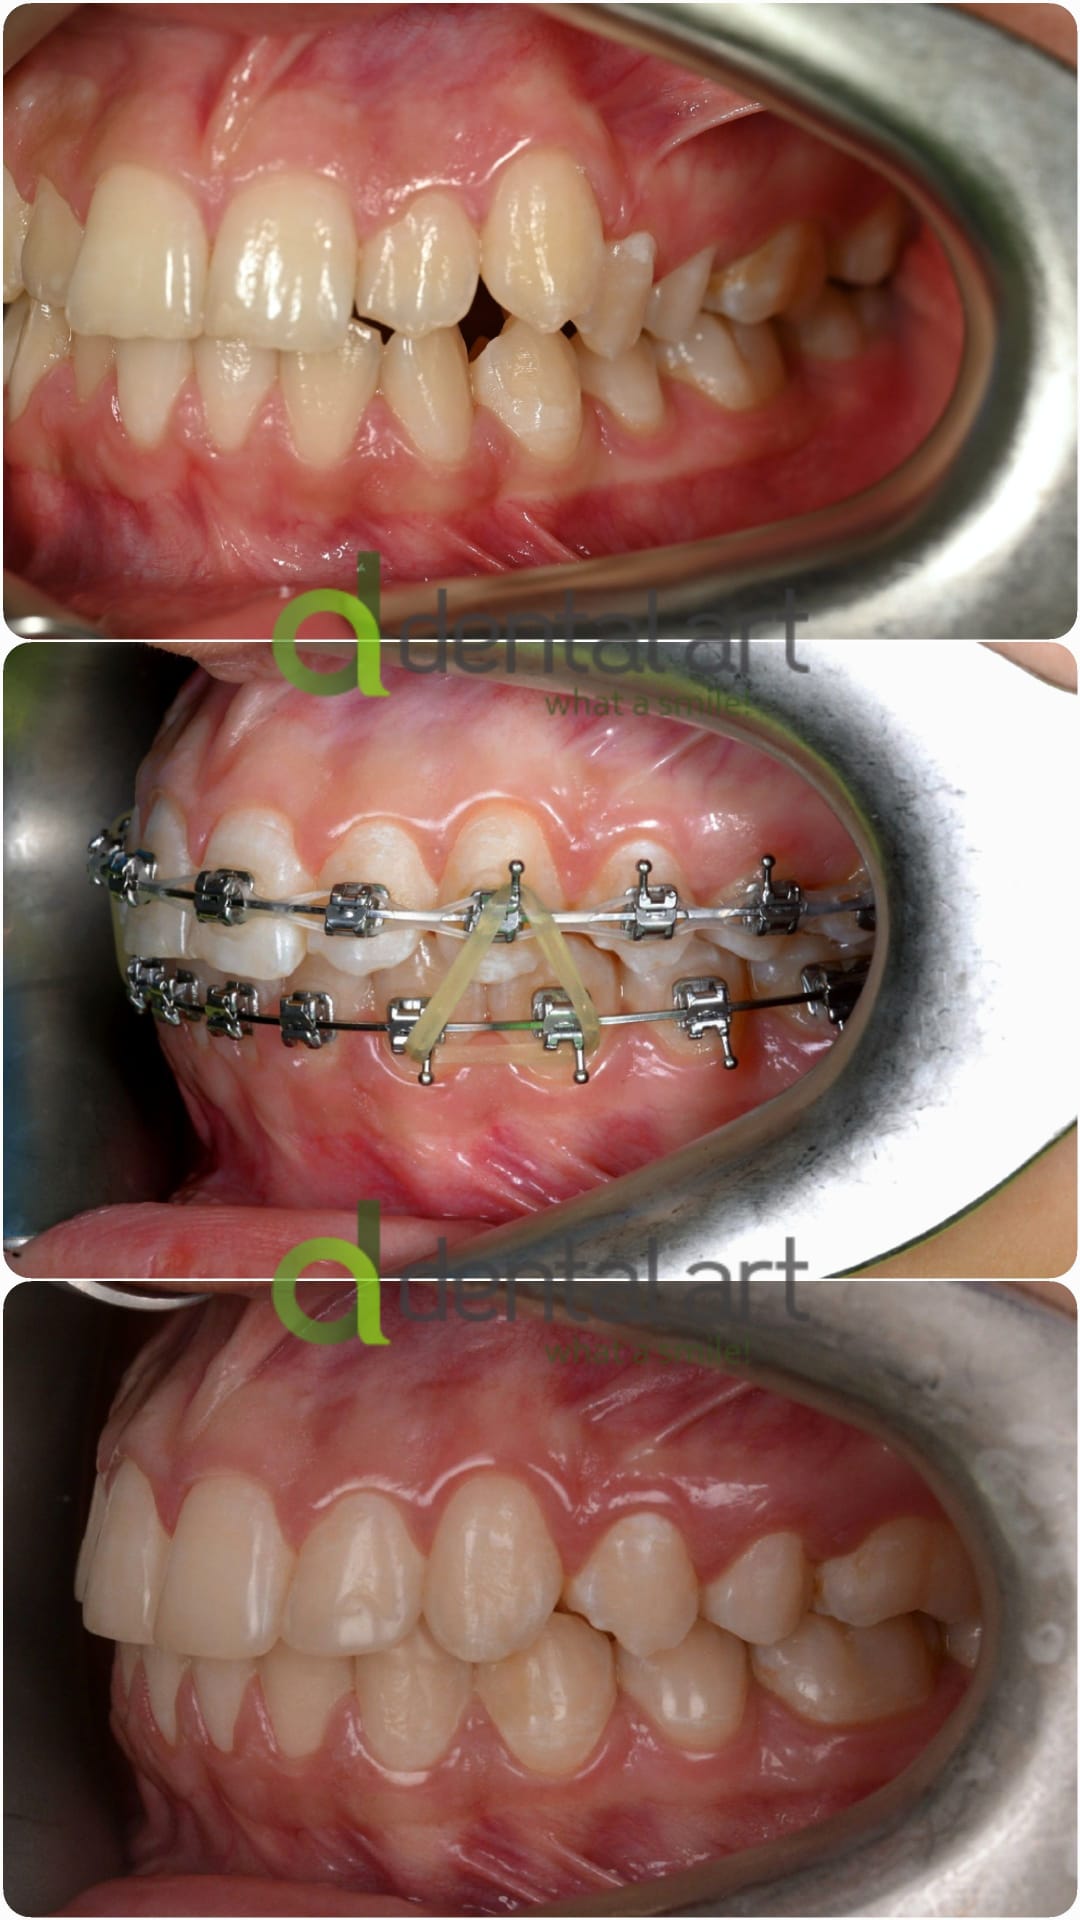

Sunt benzi elastice mici, din latex, folosite pentru corectarea mușcăturii și intercuspidarea dinților.

Elasticele se atașează de brackeții dinților superiori, respectiv inferiori și vin în diferite dimensiuni și grade de forță.

![]() | ![]() |

Elasticele ortodontice corectează raportul dintre maxilar și mandibulă (mușcătura). Sunt purtate conform indicațiilor medicului și sunt esențiale în multe tratamente pentru alinierea corectă a arcadelor.